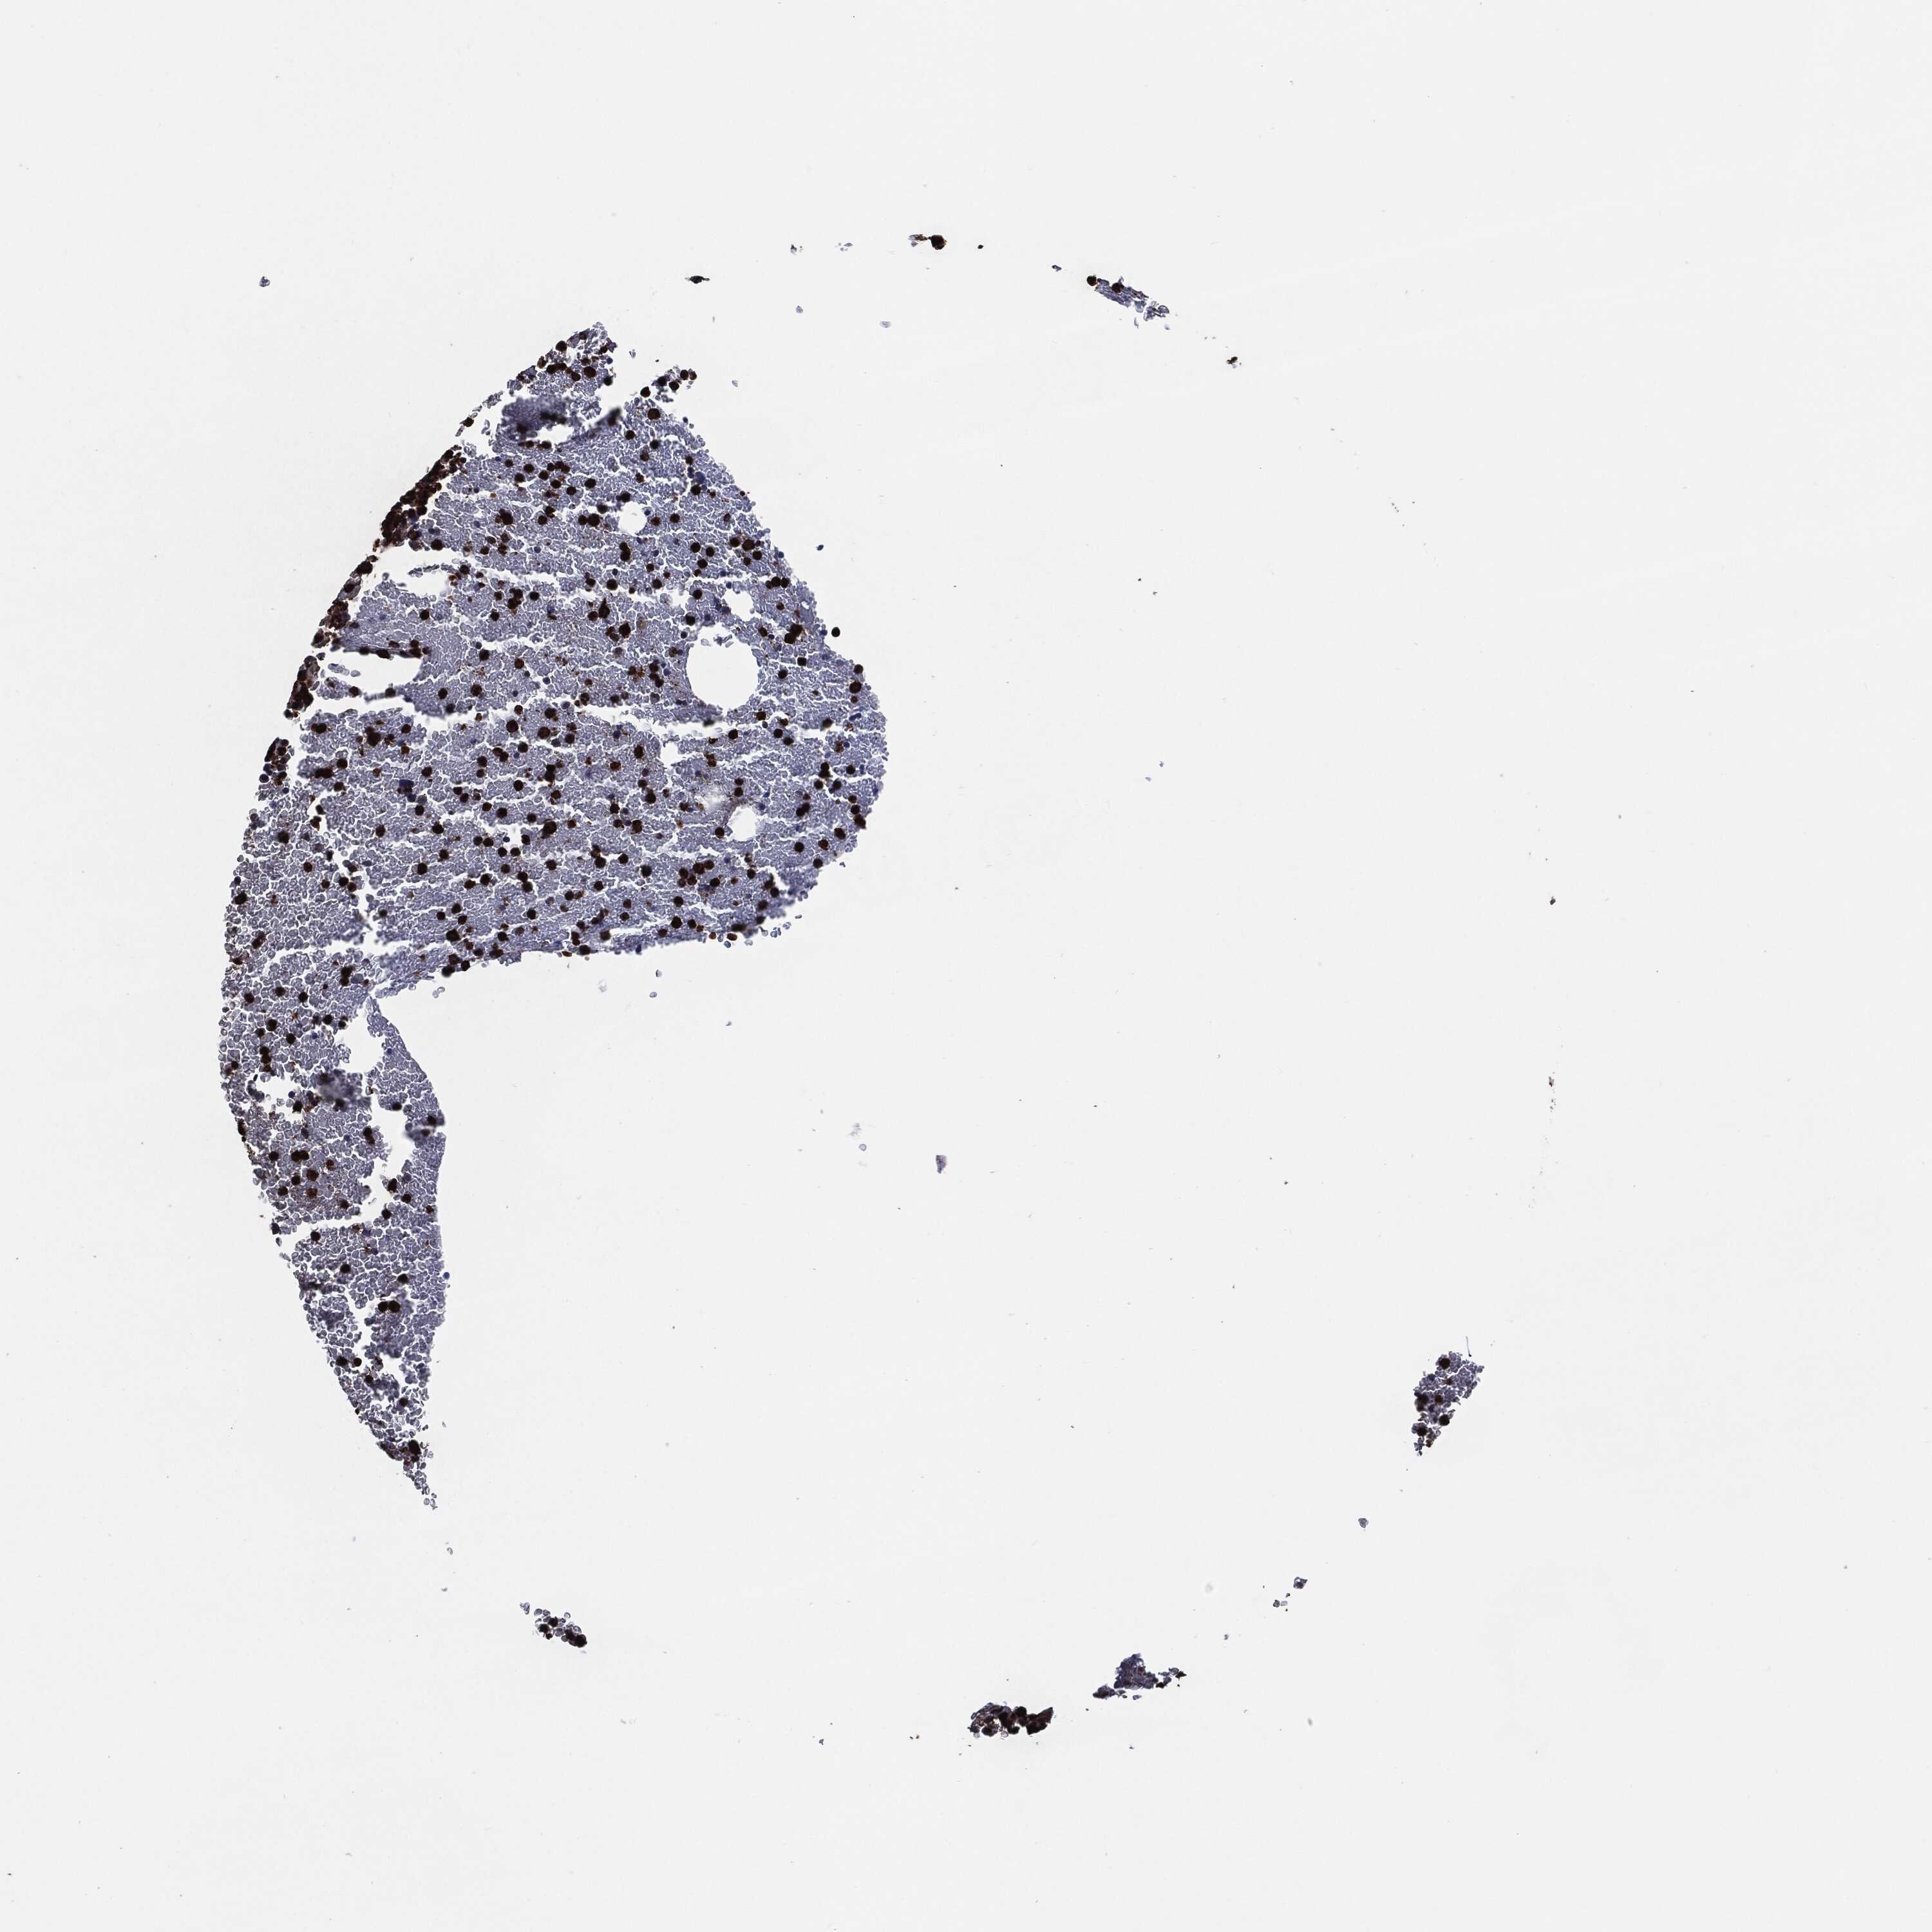

BONE MARROW - Antibody stainingi

Antibody staining in the annotated cell types in the current human tissue is reported as not detected, low, medium, or high, based on conventional immunohistochemistry profiling in selected tissues. This score is based on the combination of the staining intensity and fraction of stained cells.

Each image is clickable and will lead to virtual microscopy that enables deeper exploration of all samples and also displays staining intensity scores, fraction scores and subcellular localization as well as patient and tissue information for each sample.

Antibody HPA021147Antibody HPA061464Antibody CAB000059Antibody CAB080352Antibody CAB080353Antibody CAB080354

Hematopoietic cells LowHighMediumHighHighHigh

BONE MARROW - HPA RNA-seqi

The RNA-seq details section shows detailed information about the individual samples used for the transcript profiling and results of the RNA-seq analysis.

Information about each individual sample is listed below, including gender, age, a tissue section image and estimated fractions of cell types. nTPM (normalized transcripts per million) values give a quantification of the gene abundance which is comparable between different genes and samples.